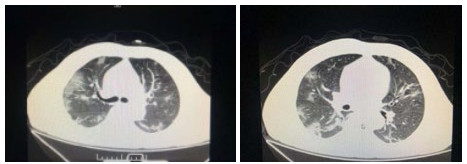

| 图 7 患者,女性,36岁,沪籍,有武汉流行病学接触史。发热8 d伴咳嗽,咳痰,有头胀痛,体温38.5℃, 白细胞总数21.8×109/L,淋巴细胞计数10.4%,甲型流感筛查阴性,流感病毒B型IgM阳性,新型冠状病毒核酸检测2次阴性。肺部CT提示双肺多发团片影,实变及磨玻璃结节,伴支气管充气征。诊断乙型流感病毒性肺炎 Fig 7 Case 7, female, 36 years old, born in Shanghai, with a history of epidemic exposure of Wuhan. She had fever for 8 days with cough, expectoration, head pain, body temperature of 38.5℃, total white blood cells of 21.8×109/L, lymphocyte count of 10.4%, negative influenza A virus screening, positive influenza B IgM, and negative novel coronavirus nucleic acid test for twice. Lung CT showed multiple mass shadows, consolidation and ground glass nodule in both lungs, accompanied by bronchiectasis. She was diagnosed as influenza B pneumonia |

| 图 8 患者,男性,20岁,湖北籍,发病前6 d有武汉流行病学接触史,发热,体温39.3℃,有干咳,血白细胞总数及淋巴计数正常,甲型、乙型流感病毒抗原筛查阴性以及其他呼吸道常规病毒筛查阴性,新型冠状病毒核酸检测2次阴性。肺部CT提示左下肺磨玻璃结节,贴近胸膜,可见铺路石征,小叶间胸膜增厚。病因不明 Fig 8 Case 8, male, 20 years old, born in Hubei Province, had a history of epidemic exposure of Wuhan 6 days before the onset of the disease. He had fever with a body temperature of 39.3 ℃, dry cough, normal WBC and lymph count, negative influenza A and B virus screening, and other routine respiratory virus screening, negative novel coronavirus nucleic acid test for twice. Lung CT showed ground glass nodule of the lower left lung, close to the pleura, with paving stone sign and thickening of interlobular pleura. Unknown etiology |